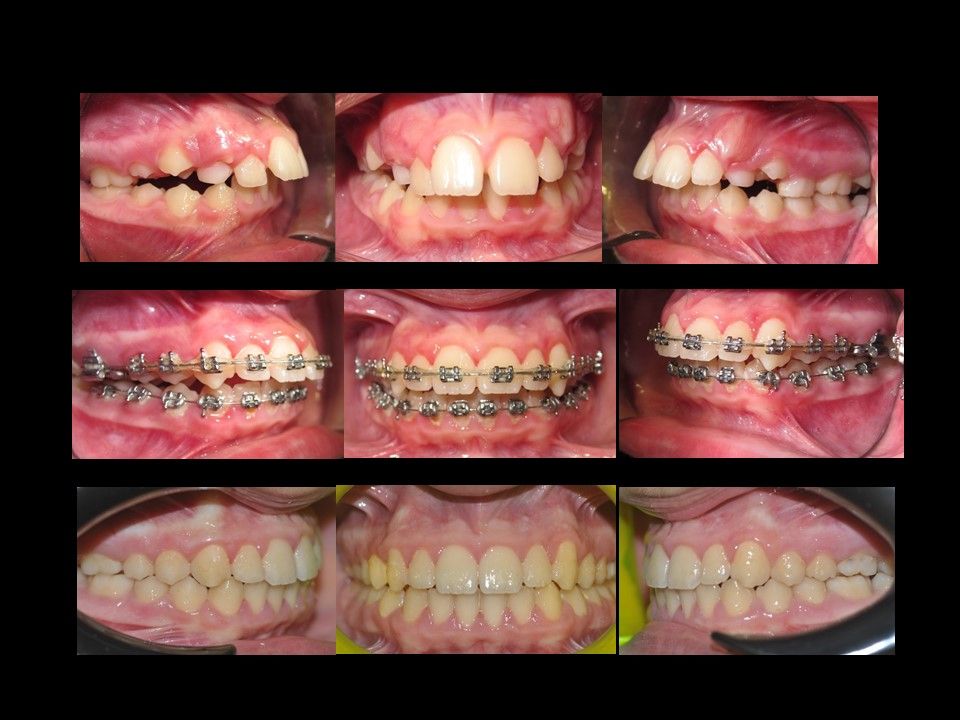

Il dottor Gianluca del Vecchio si occupa esclusivamente di ortognatodonzia, grazie anche alla collaborazione multidisciplinare di una équipe davvero entusiasmante e all’utilizzo di strumenti diagnostici e terapeutici all’avanguardia in ortognatodonzia. Particolare è la sua capacità di condurre i giovani pazienti ad affrontare, nella massima sicurezza emotiva e clinica, qualsiasi eventuale condizione di dolore derivante, ad esempio, da carie o da altre patologie, ma soprattutto di risolvere tutte quelle condizioni di “denti storti”, così spesso causa di disagio psicologico o di fenomeni deprecabili, quale il bullismo.

Queste le ragioni che consentono di trattare le malocclusioni, sia dei bambini che degli adulti, con protocolli scientificamente validati come i più veloci, affidabili e confortevoli.

Il dottore ha acquisito una concezione quanto più pratica e moderna della disciplina e utilizza apparecchietti di diversi colori di tipo mobile e fisso, ma anche terapie sia estetiche che invisibili, fiore all’occhiello di poche realtà in Italia. Per terapie estetiche e invisibili si intendono quelle in grado di spostare i denti, senza che traspaia nulla dalla bocca o con stelline e fili bianchi, esattamente come i denti del paziente.